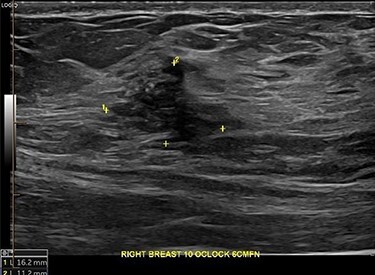

Core biopsy of the right breast demonstrated a high-grade ductal carcinoma in situ (DCIS) (Fig. 4), whilst staging computed tomography and bone scan showed no evidence of distal disease. Magnetic resonance imaging (MRI) identified a resectable 60-mm area in the right outer quadrant. AB underwent an oncoplastic right wide local excision with sentinel lymph node biopsy (SLNB), subsequently requiring an axillary dissection due to macrometastatic axillary disease. Histopathology showed multifocal high-grade invasive ductal carcinoma with immunotyping of Grade 3, PR ++, HER-2 negative, resulting in an adjuvant chemotherapy regime of cyclophosphamide and doxorubicin. The left breast was monitored without change during this time. Fully fractionated whole breast radiotherapy with boost to the tumor bed and regional lymph nodes is scheduled, alongside risk reducing endocrine therapy.

Figure 4 .

Right breast lesion visible on USS.